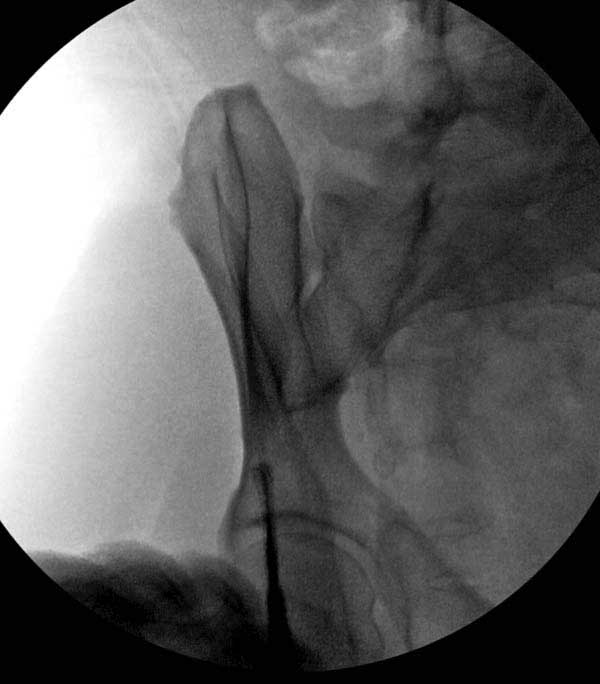

Представлены снимки техники проведения стержней. Через место прикрепления прямой мышцы в Inferior Iliac Spine в направления вырезки создается жесткость. Weber clamp изнутри таза для репозиции, и фиксация после репозиции перелома крыла подвздошной кости. Наружный аппарат удален, нагрузка предполагается через два месяца.